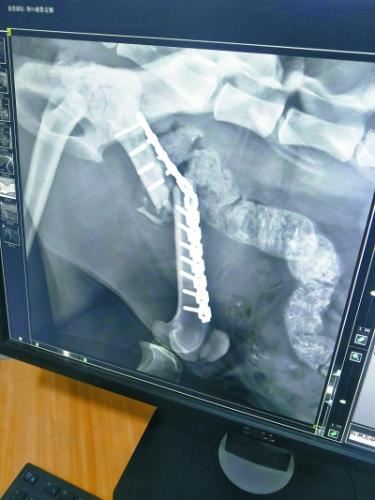

今年1月23日,饲养员发现“凌雪”步态异常,似乎又不能用力了。饲养员随即联系兽医,将“凌雪”麻醉后再次拉到动物医院拍片,结果令所有人大吃一惊,同时也心底一凉:“凌雪”左后肢股骨的加固钢钉折断了3根,钢板扭曲,股骨再次移位,它的腿又断了!

第一次手术植入的钢钉折断了3根

考虑到“凌雪”年事已高,已经打过11根钢钉,再次利用钢钉的话,可能会骨骼碎裂。而产生的碎骨还可能对肌肉等组织造成二次伤害,甚至感染致命。西宁野生动物园曾组织兽医和动物医院的医生进行了讨论,又向青海三甲医院的骨科专家进行了咨询,同时还向国内资深的野生动物救护人员、动物园兽医求教,但大家的意见差别很大。